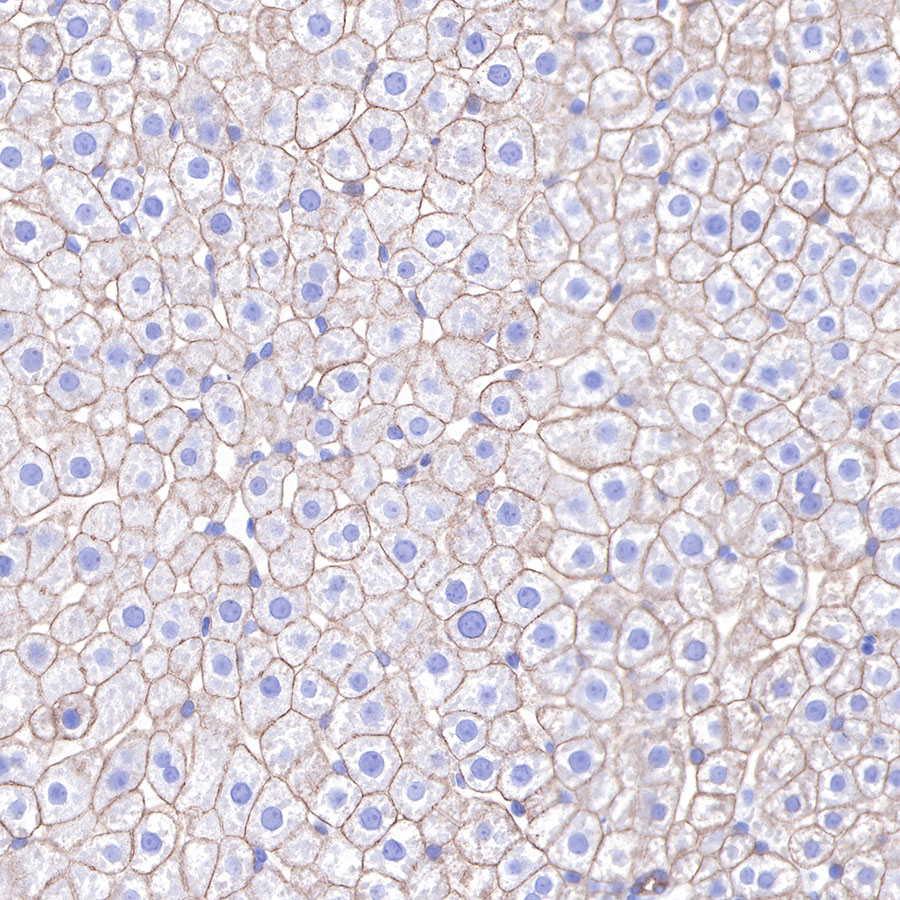

| IHC-P |

1:2000 |

Cytokeratins are proteins of cytoskeletal intermediate filaments, and their main function is to enable cells to withstand mechanical stress. In humans, 20 different cytokeratin isotypes have been identified. Cytokeratins 8, 18, 19, and 20 have been associated with bladder. Cytokeratin 18 (KRT18, also called K18), found in epithelial cells, is released from hepatocytes upon death.